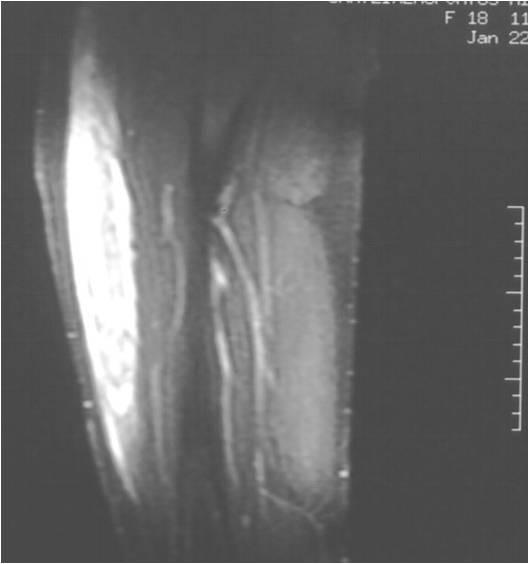

We report the case of a 21-year-old Greek Caucasian female rowing athlete who was injured on both thighs. She complained of pain and inability to walk. Physical examination revealed tenderness over the thighs and restriction of knee movement. The result of a roentgenogram was normal, and there was no evidence of fracture or patella displacement. Magnetic resonance imaging revealed haematoma formation in both the rectus femoris muscles. The diameters of the left and right haematomas within the muscles were 6 cm and 5 cm, respectively. Therapeutic approaches included compression bandages, ice application, rest, elevation, and administration of muscle relaxant drugs. Active stretching and isometric exercises were performed after three days. The patient was able to walk using crutches two days after the initiation of treatment. On the seventh day, she had regained her full ability to walk without crutches. Non-steroidal anti-inflammatory drugs were administered on the fifth day and continued for one week. Six weeks later, she had pain-free function and the result of magnetic resonance imaging was normal. She was able to resume her training programme and two weeks later, she returned to her previous sport activities and competitions.

我们报告一例21岁的希腊白人女性赛艇运动员双侧大腿受伤的病例。她主诉疼痛且无法行走。体格检查发现大腿压痛及膝关节活动受限。X线检查结果正常,无骨折或髌骨移位迹象。磁共振成像显示双侧股直肌均有血肿形成。肌肉内左侧和右侧血肿直径分别为6厘米和5厘米。治疗方法包括加压包扎、冰敷、休息、抬高患肢以及给予肌肉松弛药物。三天后进行主动拉伸和等长运动。治疗开始两天后患者能够借助拐杖行走。第七天,她已完全恢复不用拐杖行走的能力。第五天给予非甾体类抗炎药并持续一周。六周后,她功能正常且无疼痛,磁共振成像结果也正常。她能够恢复训练计划,两周后,她重返之前的体育活动和比赛。